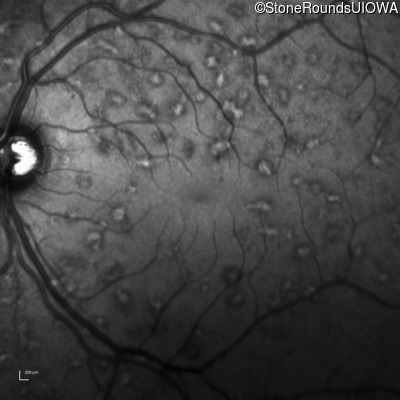

Infrared Fundus Photograph - Right - 20/15 -1 sc

Exemplar